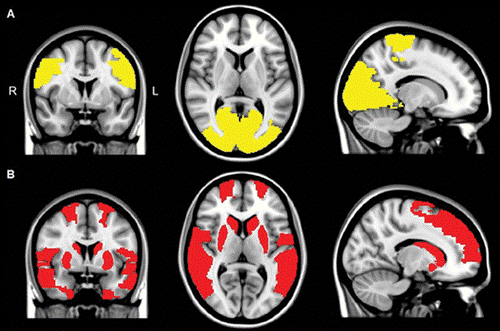

фМРТ-изображения показывают снижение региональных функциональных связей у пациентов с БП (А) и у пациентов с БП и галлюцинациями (В). Анализ функциональной связности покахывает более слабую связь у пациентов В, а также А по сравнению с контрольной группой в парацентральной и затылочной областях (показано желтым). Функциональные связи во фронтальной, височной и подкорковой областях намного ниже у пациентов В по сравнению с контролем. Илл: M. Schoonheim, VUMC.

Оказалось, что у всех пациентов с болезнью Паркинсона наблюдалось снижение функциональной связности некоторых областей мозга с остальной корой (см. илл. и подпись к нему), однако у пациентов с галлюцинациями нарушение связности было особо ярко выражено. Таким образом, вероятно, что галлюцинации связаны с нарушением межнейронных связей в областях мозга, вовлеченных во внимание и обработку зрительной информации.